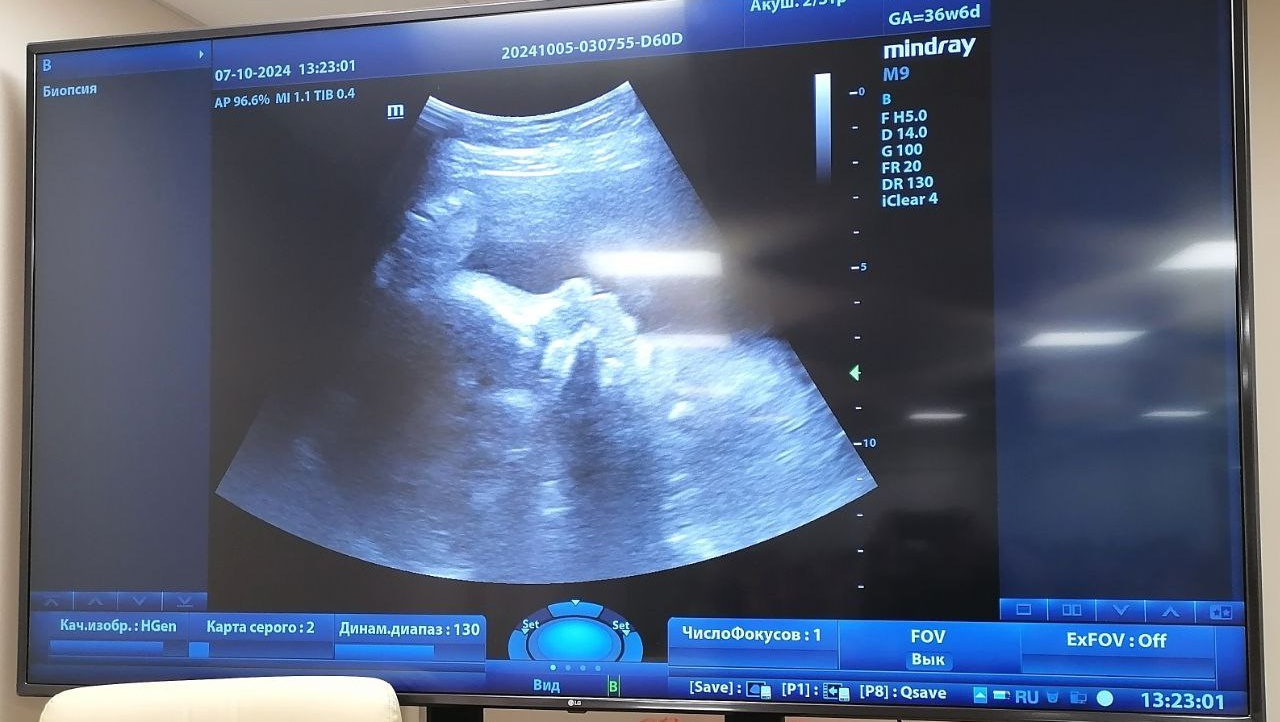

На днях в инфекционной больнице скончалась 23-летняя беременная женщина. Осложнение у неё возникло на фоне инфекционного процесса.

— Осложнение возникло на фоне инфекционного процесса, — прокомментировал Владимир Дудаков. — Помощь оказывалась ей в полном объёме. Было принято решение об экстренном родоразрешении, что, к сожалению, не привело к успеху.

Какая именно инфекция была у пациентки, а также удалось ли спасти плод, министр не уточнил, сообщает телеканал «Саратов 24» .

фото: скрин